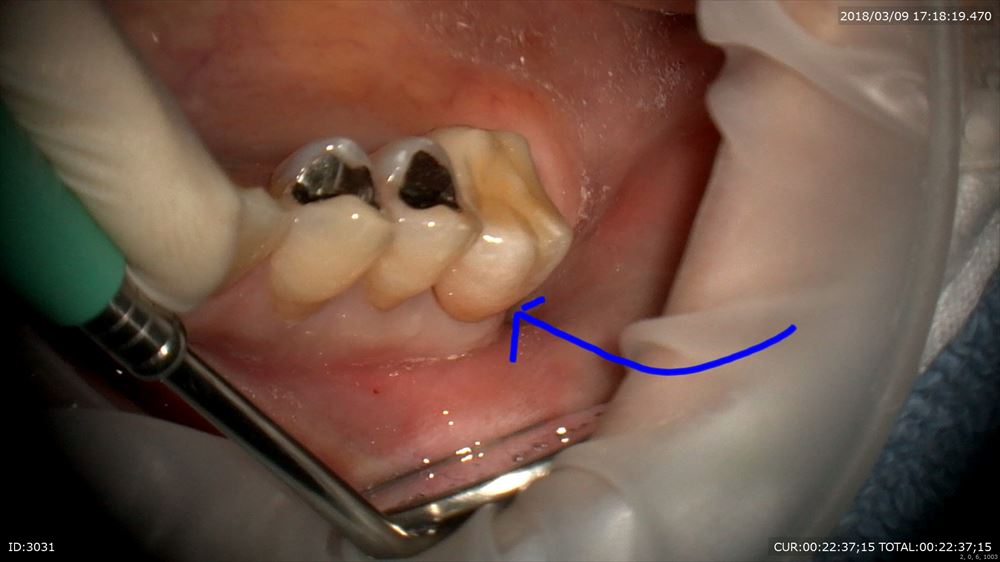

この方が1年前重症の歯周病と思えますか?

歯周基本治療と歯周外科を行い1年。こんなにきれいな歯茎になりました。